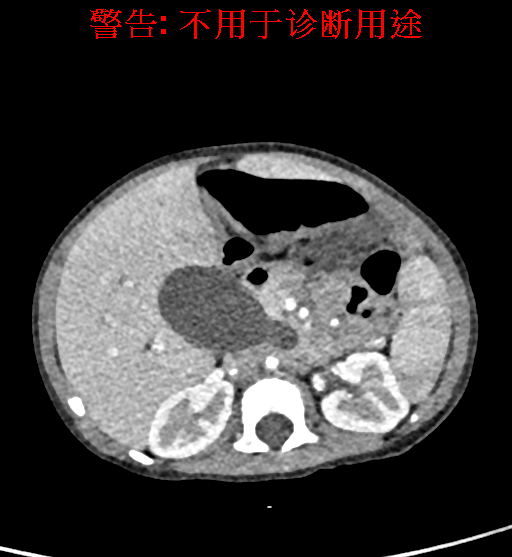

实验室检查: 血常规:WBC 16.16*109/L,NEU2.88*109/L,RBC3.76 1012/L,HB 92g/L, PLT 414*109/L 生化全套:ALT 50.00 U/L, AST 147.00 U/L, ALT/AST 0.34,LDH 367.00 U/L, ALB 36.91g/L, GGT 1297.00 U/L, ALP 1155.00 U/L, BIL-T 138.23 umol/L, BIT-D 97.01 umol/L, TBA 48.40umol/L,ADA 40.00U/L, PAB 121.40mg/L, BUN 1.98 mmol/L, CREA 17.00 umol/L 肝炎全套: 炎症反应标志物:CRP 7.27mg/l 诊疗过程: CT结果输入海信CAS系统后行3D重建及手术规划后,于2018-5-31全麻下行“胆总管囊肿切除+肝总管空肠吻合术”手术治疗: 术前三维重建及手术方案设计: 将0.625mm双源薄层CT资料的静脉期和动脉期Dicom格式文件导入海信CAS系统。 通过调节窗宽窗位调整CT序号,对肝实质,胆囊,下腔静脉,肿瘤,肝动脉、门静脉及肝静脉等进行三维重建;系统自动计算肝脏体积,肝脏体积为648.3ml,通过术前模拟手术,精准判断手术切除范围,进行精密术前规划及讨论后实施手术。 手术步骤: 麻醉成功后,患儿取平卧位,2.5%碘伏消毒手术区皮肤,铺无菌巾单。取右上腹纵口长约5m,切开皮肤、皮下织组,腹直肌前鞘、腹直肌,后鞘和腹膜。探查见:胆总管3×2cm大小,胆囊管迂曲,长约10cm。 剥离、切除胆囊,游离胆总管,将之横断:①近端即肝总管,剪裁后被吻合用;②远端游离切除囊肿内壁,直至胆总管开口于十二指肠处,冲洗后予以结扎缝扎。距treits韧带20cm处横断空肠:①近端与其远端25cm处的空肠侧壁行端侧双层吻合,吻合口通畅;②远端断端封闭,其侧壁剪开,并经横结肠后提至肝门处,与剪裁的肝总管行端侧双层吻合。缝合修补胆囊床及系膜裂孔,肝门部放置橡胶引流管一根。温盐水冲洗腹腔。检查无活动性出血,清点纱布器械无误,依次缝合腹壁各层。手术顺利,麻醉满意,出血不多,未输血,术后病人先进入麻醉恢复室,苏醒后回病房。手术时术者可开启Hisense CAS系统手势控制功能,对肝脏及胆囊解剖结构进行实时、全方观察、评估,起到术中导航作用。 术后病理: 1. (囊肿壁)囊肿性病变,囊壁部分区域衬覆柱状上皮。 2. 慢性胆囊炎。 3. 送检(肝门)淋巴结查见淋巴结1枚,呈反应性增生。 随访情况: 患儿术后2周恢复良好 术前CT检查:动脉期

平衡期